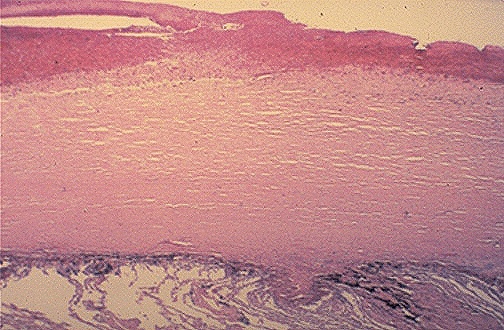

Microscopically, the fibrous pleural plaque is composed of dense layers of collagen that give a pink appearance with H&E staining and a white to tan appearance grossly.